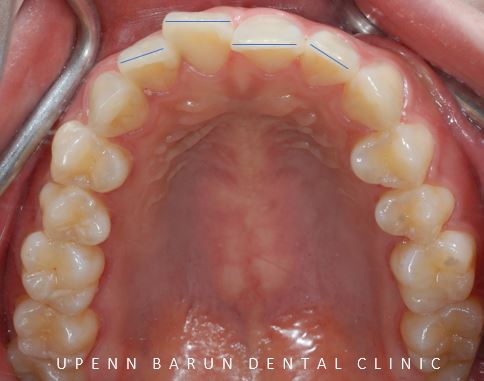

교합면에서 바라봤을때는 치아끼리 이은 선이

삐뚤빼뚤한 양상을 보였습니다.

삐뚤빼뚤했던 앞니들이

잠실교정치과 유펜바른치과의

인비절라인 28개의 장치로

올바르게 배열되었습니다.

교정완료 후에는 틀어짐을 방지하기 위해

안쪽에 유지장치로 마무리 해드렸습니다 :)